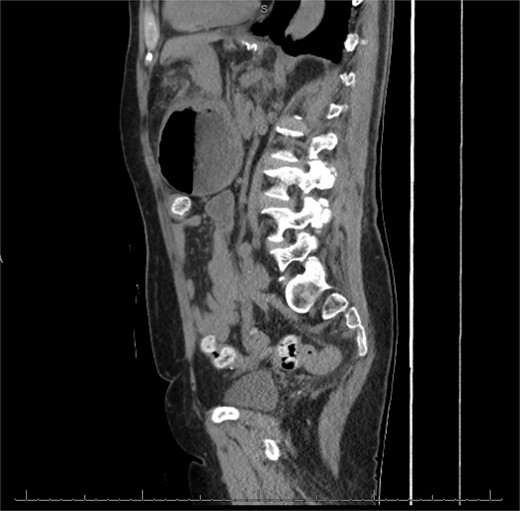

The patient was a 74-year-old female with a history of hypertension, chronic migraines, hiatal hernia repair with Nissen fundoplication repair, and cecal volvulus treated with right hemicolectomy who presented with abdominal pain, nausea, and vomiting. Six months prior, she exhibited symptoms of bloating and nausea, which were treated with oral Reglan with some improvement. She reported vomiting episodes for 2 months that acutely worsened over the 4 days prior to presentation. Examination revealed a soft and mildly distended abdomen with tenderness in the epigastrium and left upper quadrant. Initial vital signs showed a temperature of 36.1°C, blood pressure of 149/88 mmHg, heart rate of 115 beats/min, and oxygen saturation of 95% on room air; tachycardia resolved with resuscitation. Labs were notable for a white blood cell count of 8.8 × 1000/mcL and hemoglobin of 14.2 g/dL. Sodium was 137 mEq/L, potassium was 3.3 mEq/L, and creatinine was 0.75 mg/dL. Computed tomography (CT) of the abdomen and pelvis (Figs 1 and 2) showed gastric volvulus without pneumatosis, significant wall thickening, or distention. Nasogastric tube was placed. An upper gastrointestinal fluoroscopy scan showed no passage of contrast beyond the stomach and demonstrated 90° rotation of the stomach (see Fig. 3). The patient underwent surgery that same day.

Sagittal view of CT scan of abdomen and pelvis demonstrating gastric volvulus.